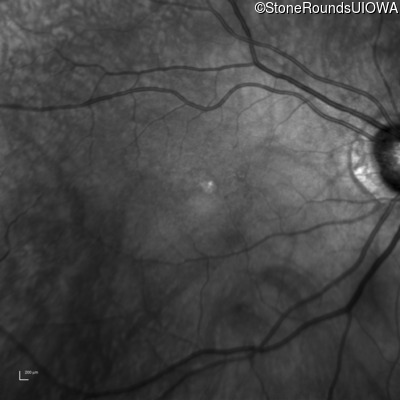

This 70 year old woman first noticed some reduction in visual acuity in both eyes at age 45. Her visual acuity had been previously normal.

The clinical features favoring the diagnosis of RP1L1-associated occult macular dystrophy include: reduced acuity with a near-normal ophthalmoscopic appearance, a history of normal acuity in childhood; and, a "moth-eaten" appearance of the macular ellipsoid zone on OCT.